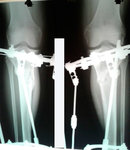

Исходник - 28 лет.

Дата операции 31.08.2016г.

У пациентки круропластика. Ситуация не ординарная, т.к. исправляем не деформацию, а внутреннюю ротацию (двойную) 45 градусов. Из за неё, у девочки после нагрузки - боли в ногах и при ходьбе - стопы бросает во внутрь.

в процессе исправления ротации.